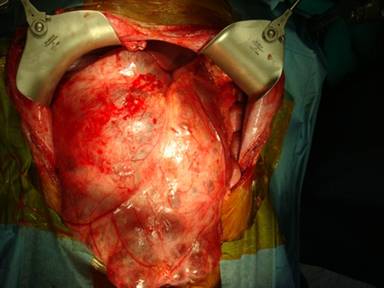

At laparotomy the peritoneal cavity was found to be fully occupied by a multicystic, septate mass (approximately 30x50 cm) containing a clear yellowish fluid, arising from the head of the pancreas, adherent to the transverse colon, mesocolon, duodenum and stomach (Figure 3). The mass was inseparable from the antrum of the stomach, the duodenum and the head of the pancreas. There were no ascites or peritoneal or liver nodules. The mesenteric and peripancreatic lymph nodes were enlarged. A classic Whipple pancreaticoduodenectomy was carried out (Figure 4).

Figure 3. Operative photograph showing the tumor. |